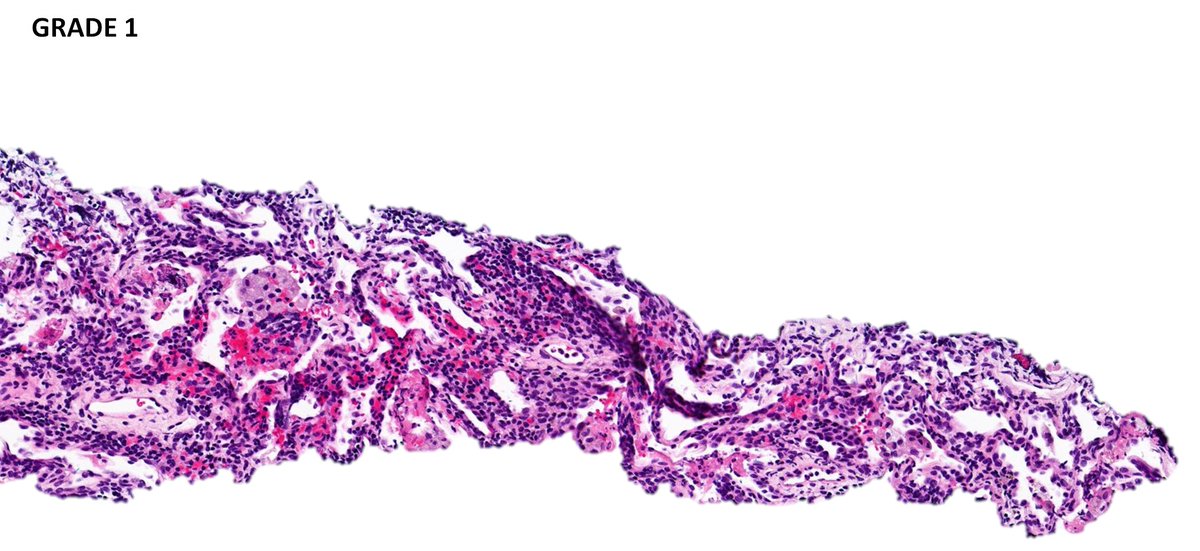

Lung biopsy illustrating a spectrum of involvement by lymphomatoid granulomatosis➡️ 🩸Grade 1: Polymorphous angicentric lymphoid infiltrate without significant atypia; necrosis is absent. Large EBV-positive lymphoid cells are rare. #hemepath #lymsm #thoracicpath #PathTwitter